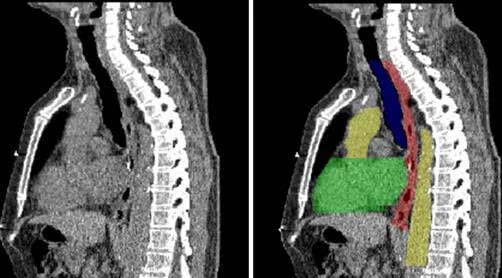

图示: 胸腔CT切片,左边是CT影像,右边是分割后的结果。其中,绿色区域对应心脏,黄色区域对应主动脉,蓝色区域对应气管,红色区域对应食管

由腾讯优图TencentX团队提出的胸部多器官分割系统,提供了一种全自动化的基于卷积神经网络结构的健康器官分割方法,能够精确快速地分割出胸腔内位于靶肿瘤附近的健康器官。利用40组CT图像训练,通过快速定位模块和精细分割网络两个阶段实现。首先通过缩小三维CT影像空间距离采样,配合3D卷积神经网络实现快速定位。接着利用2.5D卷积神经网络沿矢状面、冠状面和水平面三个方向逐层预测结果,同时与3D卷积神经网络在完整的VOI下直接预测出的结果相结合,产生准确而又全面的多器官分割结果,实现精细分割。这种先定位后分割的策略,不仅为最终的分割任务排除了大量的干扰,而且节省了计算资源。